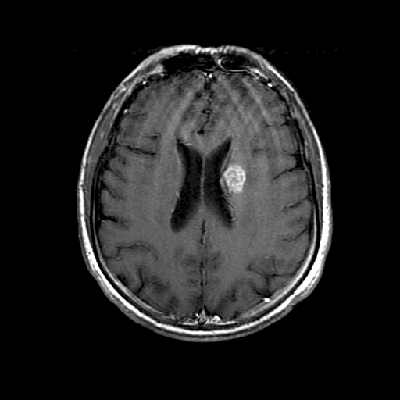

Neurologic and mental examination showed intact immediate memory but inability to recall 3 objects in 5 minutes. He was not oriented to time or space or situation but oriented to person. His remote memory was intact. There was left superior quadrantonopsia but no focal motor or sensory deficits. FLAIR images on MRI showed a lesion in the left mesial temporal lobe (Panel 1). This lesion had increased T2 signal but without enhancement on T1 images. This lesion also had mass-effect and edema within that region. On FLAIR images, there were some small foci of abnormal signal in the white matter of the right parietal lobe (Panel 2) but these foci did not enhance (Panel 3). There is a vague, poorly demarcated, triangular shaped periventricular signal abnormality in the left parietal lobe (Panel 2) but this area did not enhance (Panel 3). On another image (obtained higher to Panel 2 and 3), however, there is a small cluster of enhancing spotty signal in the white matter of the left parietal lobe (Panel 4) and the largest focus is about 0.4 cm in diameter. There were areas with features of encephalomalacia in his right mesial temporal lobe that would be explained by his history of prior infarct.

3. T1+Contrast |